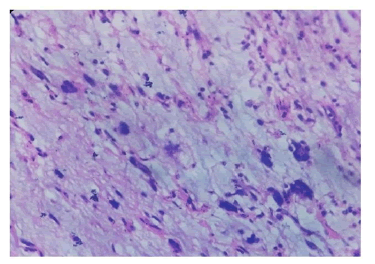

Figure 2: Myxoid MFH H and E (10 x 40) showing a neoplasm composed of elongated cells and giant cells with dark staining nuclei arranged in interlacing bundles and fascicles in an abundant myxoid background.

Haemangioendothelioma histopathology sections studied showed a vascular lesion composed of proliferating endothelial lined spaces and capillaries. The tumour cells were seen infiltrating skeletal muscles and widely separating it. Cells were round to oval with scanty cytoplasm and hyper chromatic nuclei, showing mild pleomorphic. Few mitotic figures and occasional tumour giant cells were seen (Figure 6).